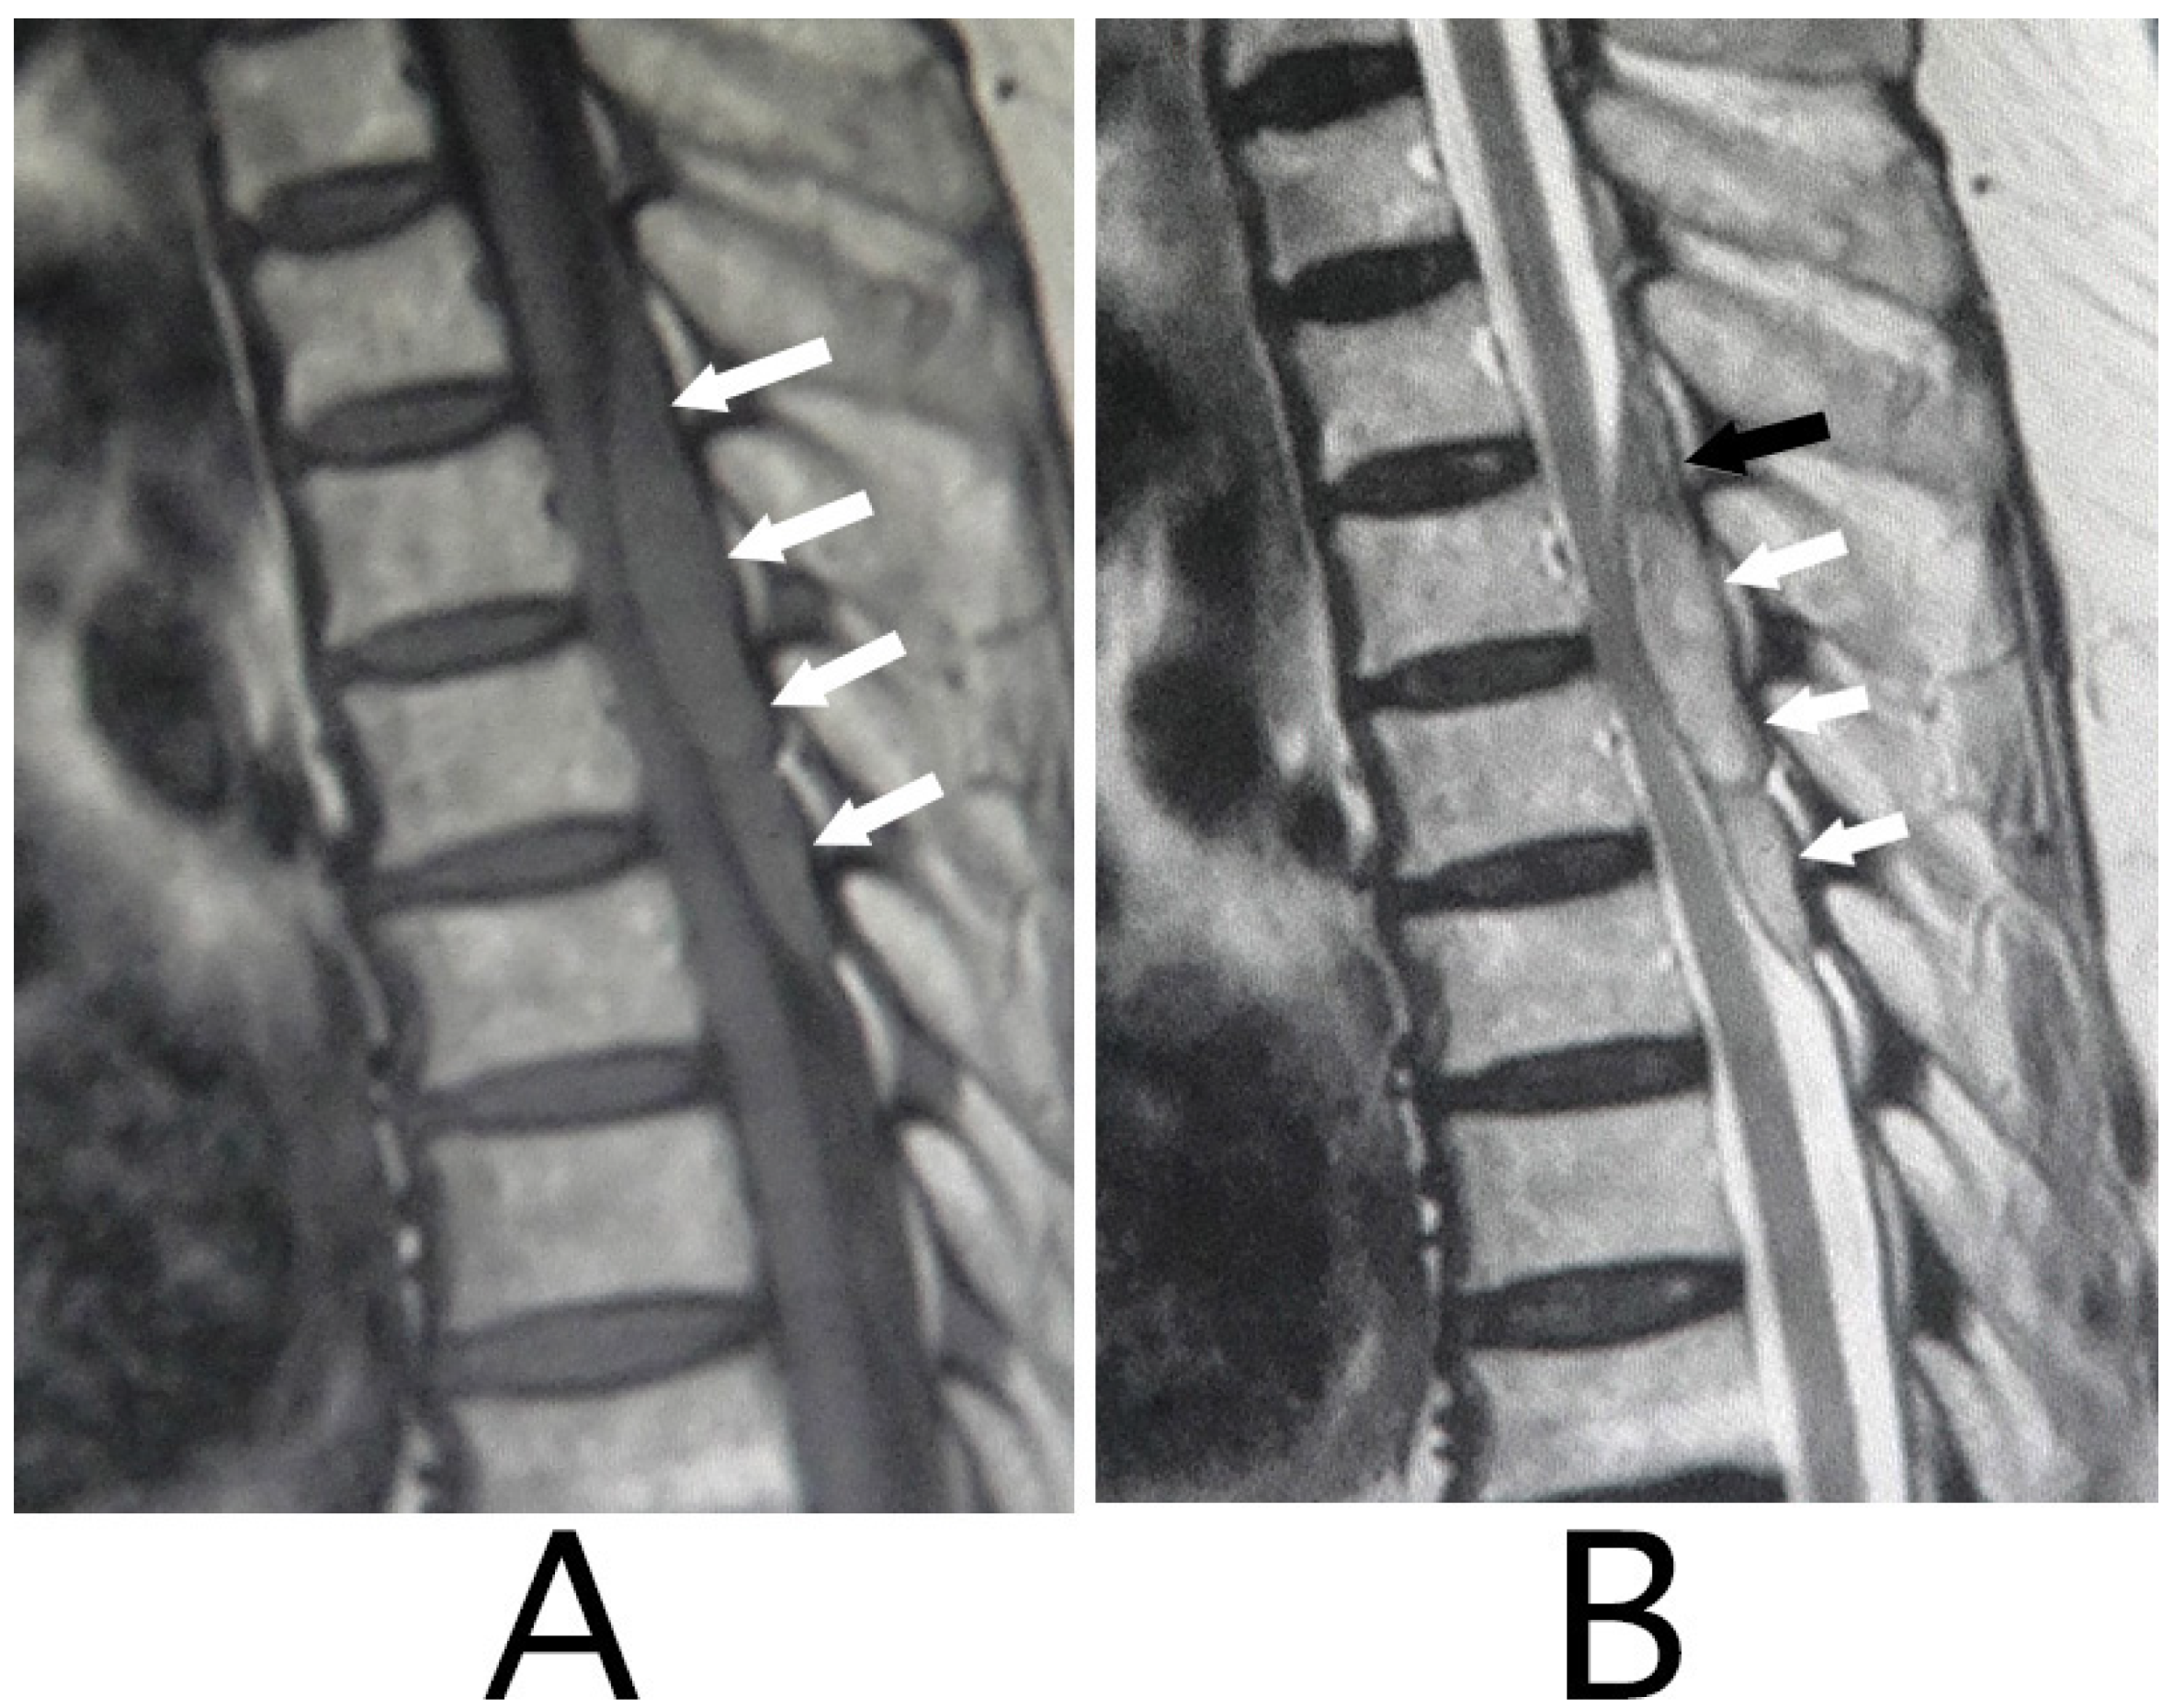

features of different causes of LETM

NMO - central often involving gray & white matter, bright & spotty, patchy enhancement, can see prominent swelling

MOG - central, sometimes restricted to gray (H sign), often non-enhancing, can involve conus

sarcoid - central, “trident” sign

paraneoplastic - tract-specific (often dorsal/lateral columns)

spinal dural AVF

present with gradual but progressive pain, leg weakness/numbness, bladder/bowel changes

flow voids on T2

can see intramedullary hyperintensity due to edema, often involving conus

confirmed with DSA